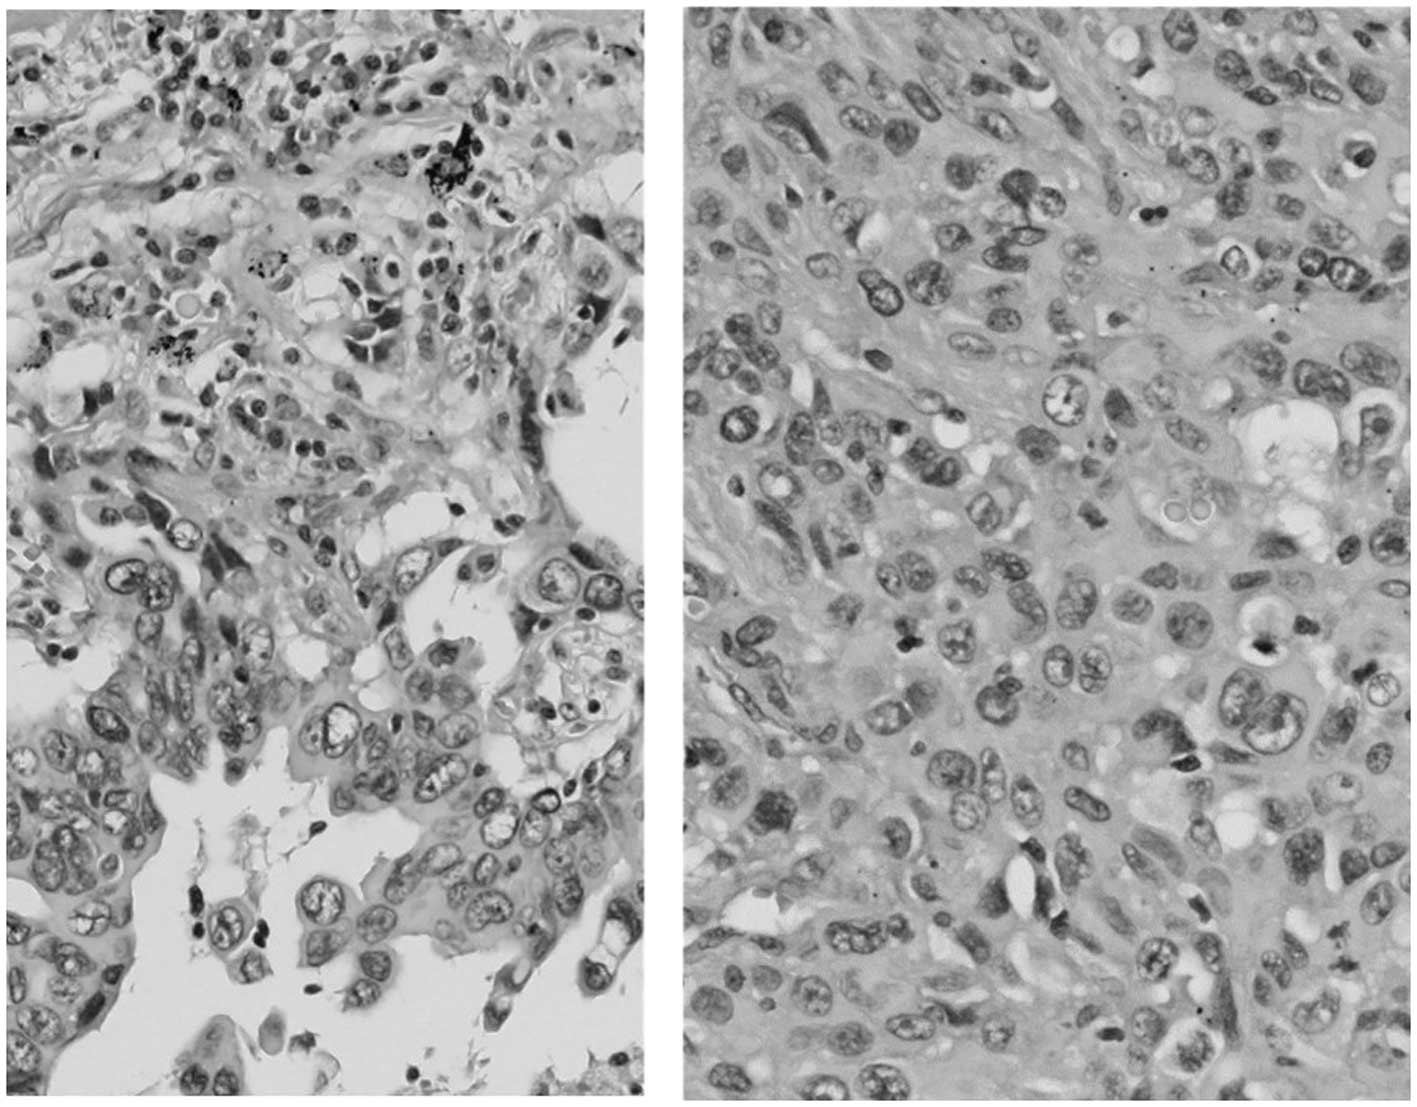

A 68-year-old man was admitted to the hospital with a productive cough. A chest radiograph revealed a tumor 5 cm in diameter in the right lung. Bioptic specimens, which were obtained transbronchially, were diagnosed as NSCLC. As the patient did not present with hilar/mediastinal lymph node enlargement or distant metastasis, he underwent right upper pulmonary lobectomy. On postoperative pathological examination, the tumor was diagnosed as pleomorphic carcinoma of the lung (Fig. 1). The examination for epidermal growth factor receptor mutations was negative. As there was microscopic involvement of the ipsilateral mediastinal lymph nodes, 4 courses of postoperative chemotherapy containing cisplatin and vinorelbine were administered. Four months after the end of the treatment (10 months after the diagnosis), the disease recurred as two pulmonary nodules ≤1 cm in diameter in the left lung, detected on follow-up chest computed tomography (CT) scan (Fig. 2). The work-up for systemic metastasis was negative. Two courses of chemotherapy, consisting of carboplatin [area under the curve (AUC) = 5, day 1, q28 days), pemetrexed (500 mg/m2, day 1, q28 days) and bevacizumab (15 mg/kg, day 1, q28 days) was performed, and the post-treatment evaluation CT scan revealed shrinkage of the two pulmonary lesions (Fig. 3). Thereafter, the patient received an additional two courses of chemotherapy. A follow-up CT scan revealed further shrinkage of the pulmonary tumors. The patient received 20 courses of maintenance chemotherapy consisting of pemetrexed (500 mg/m2, day 1, q28 days) and bevacizumab (15 mg/kg, day 1, q28 days) without any severe adverse events. No recurrence was found and the patient remained well for 30 months after the initiation of the chemotherapy for recurrence; however, the patient succumbed to brain infarction.

Six months after the initiation of the chemotherapy, the patient experienced sudden abdominal pain. An abdominal CT scan revealed free air and ascitic fluid in the pouch of Douglas (Fig. 5). Although the site of perforation was not identified, the patient was diagnosed with acute peritonitis with gastrointestinal perforation and underwent emergency surgery. During the surgical procedure, a large amount of turbid ascites was found. A perforation was discovered inside the jejunum, ~33.0 cm from Treitz's ligament. An intestinal resection of ~10 cm was performed. The intraperitoneal cavity was washed with 8,000 ml saline solution and a functional end-to-end anastomosis was performed. After the operation the patient's condition improved gradually. On pathological examination, the resected tumor was diagnosed as metastatic pleomorphic carcinoma of the lung, which was negative for G-CSF immunostaining. This result may be reflective of a possibly heterogeneous tumor population, in which metastatic tumor cells did not produce G-CSF. One month after the surgery, WBC and CRP increased to >105,100/µl and 39.06 mg/dl, respectively, and the patient succumbed to the disease 8 months after the initiation of the chemotherapy.